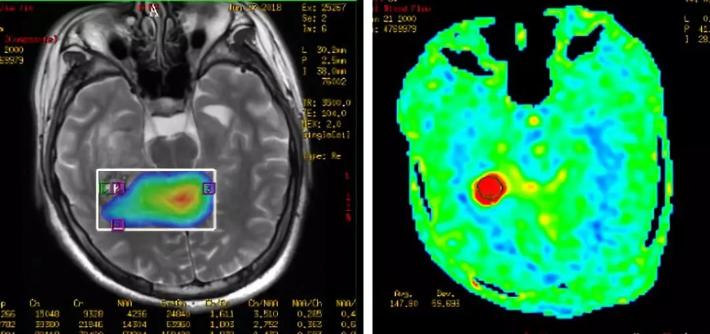

病史简介 患者男,18岁,因“久站后双小腿不自主颤动10余天”于2018.6.22入院。 患者十余天前无明显诱因下出现久站后双小腿不自主颤动,呈无力状。休息后可缓解。自觉体育运动能力较前有下降(患者为体校生)。无四肢抽动、无意识丧失、无二便困难。无明确外伤史。 查体: 神清,精神软,四肢肌力V级,深浅感觉无殊。 术前检查: 入院后头颅MRI增强显示:右侧海马占位伴出血,胶质瘤考虑(图1)。MRS:右侧海马病变部位NAA峰明显降低,Cho明显升高,Cho与NAA的比值明显加大。右侧海马病变以肿瘤可能性大。ASL灌注提示右侧海马占位明显高灌注(图2)。

图2. 患者术前ASL灌注提示右侧海马占位明显高灌注。 结合病史和影像学资料,诊断首先考虑:左海马颞叶高级别胶质瘤 诊疗经过 第一次MDT讨论: 参加科室: 神经外科、放射科、放疗科。术前诊断:右颞叶高级别胶质瘤可能性大,有手术指征。可行的手术方案包括:开颅肿瘤切除和病灶立体定向活检。考虑肿瘤位于可切除部位,拟行开颅肿瘤切除术。 术中所见: 右颞叶皮层下3cm见肿瘤,色灰红,质软,血供丰富,紧贴侧脑室三角部,下缘临近小脑幕。切除肉眼可见肿瘤。冰冻病理提示:胶质瘤可能。切除标本送病理常规及分子病理检查。术后CT复查示术区肿瘤切除,无明显出血、梗死表现(图3)。